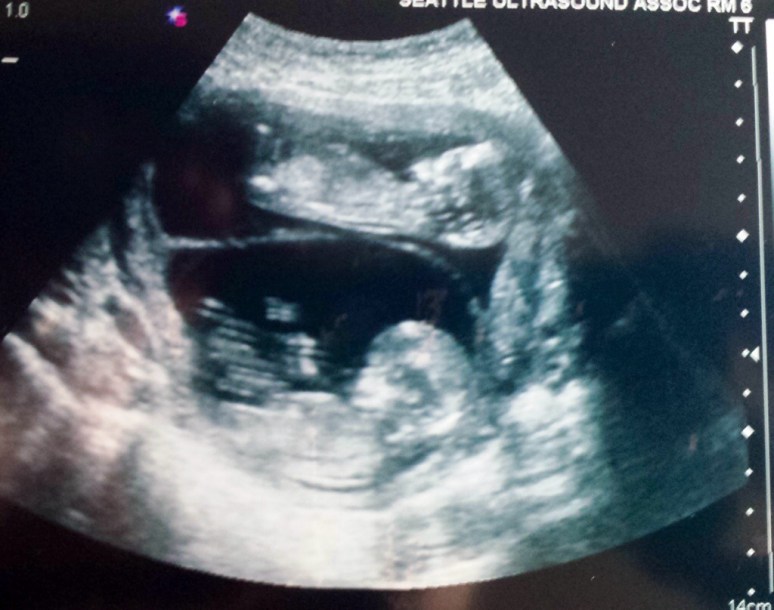

12 Week Ultrasound

Last Friday Hubby and I went to our 12 week ultrasound. At this ultrasound the babies nuchal translucency (the thickness behind the neck) was being measured to check for risk of chromosomal problems. The doctor called yesterday after reviewing our images (the ultrasound was done at a separate clinic) and said that our risk of chromosomal disorders is very low for both babies and that the risk of heart defects is low as well. Very good news!

As always, it was so exciting to see the babies. They have really grown, have little arms, legs, fingers and toes. Both were sitting in very similar positions and are measuring almost exactly the same. Baby B wasn’t nearly as active as at the last ultrasound.

Here are some pics of the little ones:

Baby A & B, Ultrasound tech said this will be the last time we’ll be able to see them together in the same image, they will be getting too big soon.